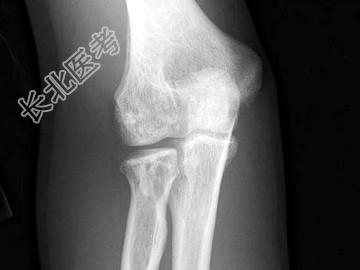

- 单项选择题男,34岁, 体检摄片如图所示,最可能的诊断是 ( )

A、氟骨症

B、转移性骨肿瘤

C、骨样骨瘤

D、骨岛

E、骨斑点症